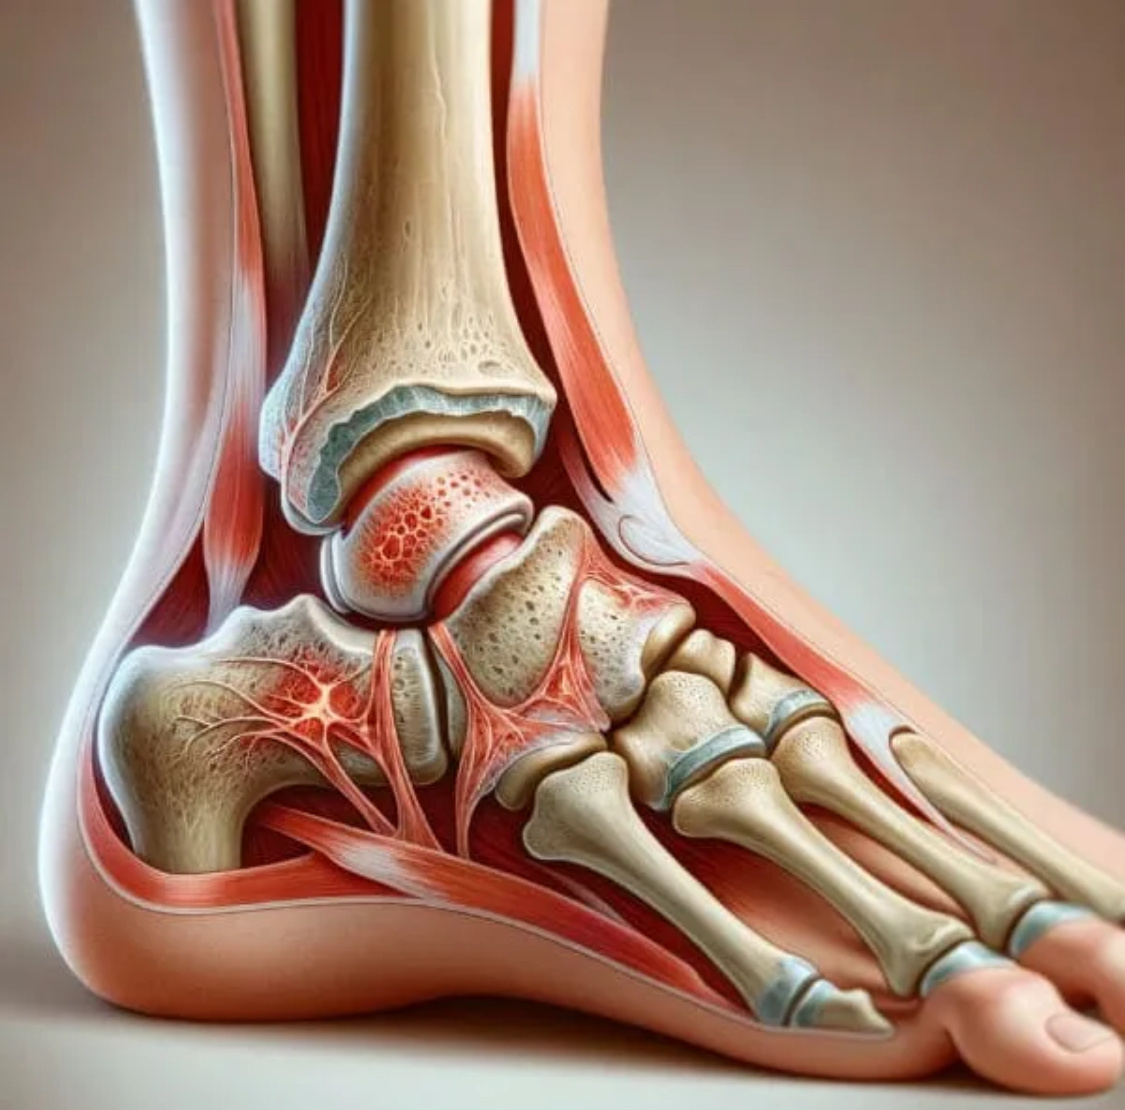

Много и часто пишу про тазобедренный и коленный суставы, стопу - это основные точки приложения ортопедии сегодня. Других локаций тоже немало, но там проблемы очень разнообразные. Одним словом, протезирование и «шишки»/косточки - это не вся ортопедия. Когда приходит пациент с чем-нибудь этаким, честно скажу - моя ортопедическая душа радуется, ибо делать рутинные операции, конечно, интересно, но нестандартные - намного интереснее. Ситуации самые неожиданные, зачастую требующие нестандартных решений. Иной раз возникает идея, она кажется оптимальной, а через сутки-другие (мозг и во сне переваривает информацию) как бы вдруг озаряет, и понимаешь - совсем по-другому надо делать - лучше, надёжнее, удобнее, проще и т.п. Да и в процессе операции нередко план меняется. Масса вариантов. Задача, по большому счёту, одна: минимальной «кровью» получить максимальный результат. После отпуска было подряд несколько историй, все на уровне голеностопного сустава, все разные. Просто для информации кое-что р

После отпуска было подряд несколько историй, все на уровне голеностопного сустава, все разные. Просто для информации кое-что расскажу, мало кто знает о таких наших (ортопедов) возможностях.